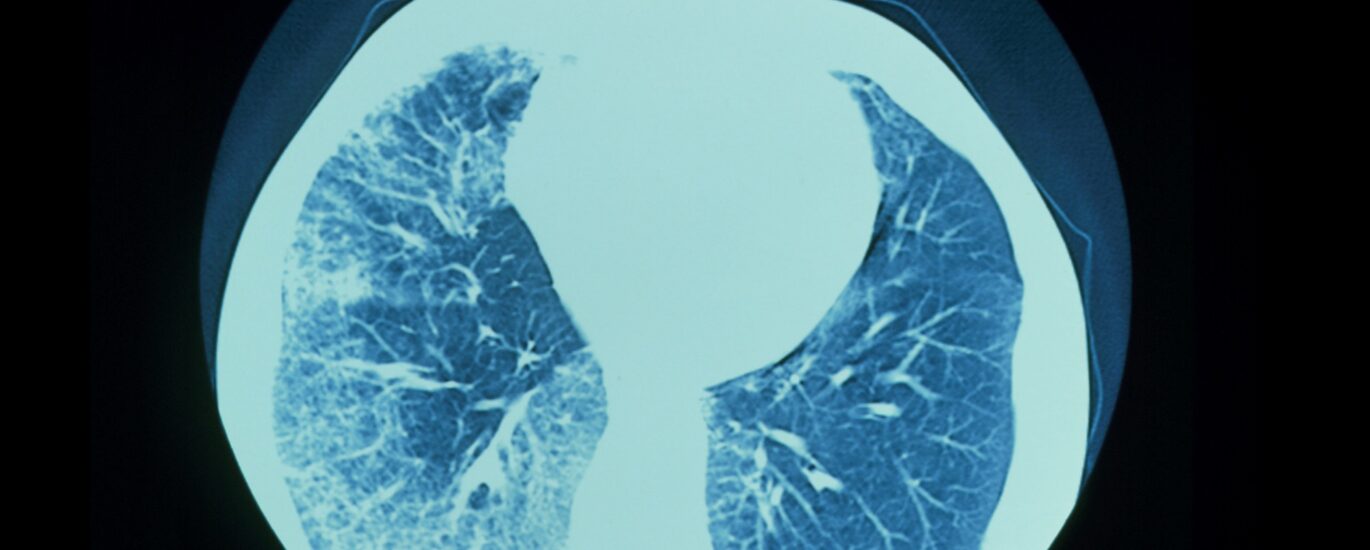

Global Progressive Fibrosing Interstitial Lung Diseases (PFILD) Treatment Industry Poised for Impressive 6.2% CAGR, Forecasting US$ 8654.1 Million Market Size by 2033 | According to FMI

The Global Progressive Fibrosing Interstitial Lung Diseases (PFILD) Treatment Industry has emerged as a pivotal sector in the global healthcare landscape, boasting a valuation of US$ 4742.2 Million in 2023. With an anticipated Compound Annual Growth Rate (CAGR) of 6.2%, experts foresee the market to surge significantly, reaching a staggering US$ 8654.1 million by 2033.

Technological advancements in healthcare stand at the forefront of this transformative journey, driving the market’s trajectory towards unprecedented heights. Factors such as the escalation in lung infections incidence, heightened awareness among the populace, and robust governmental initiatives aimed at mitigating these infections serve as key catalysts propelling the growth of the global progressive fibrosing interstitial lung disease treatment market.